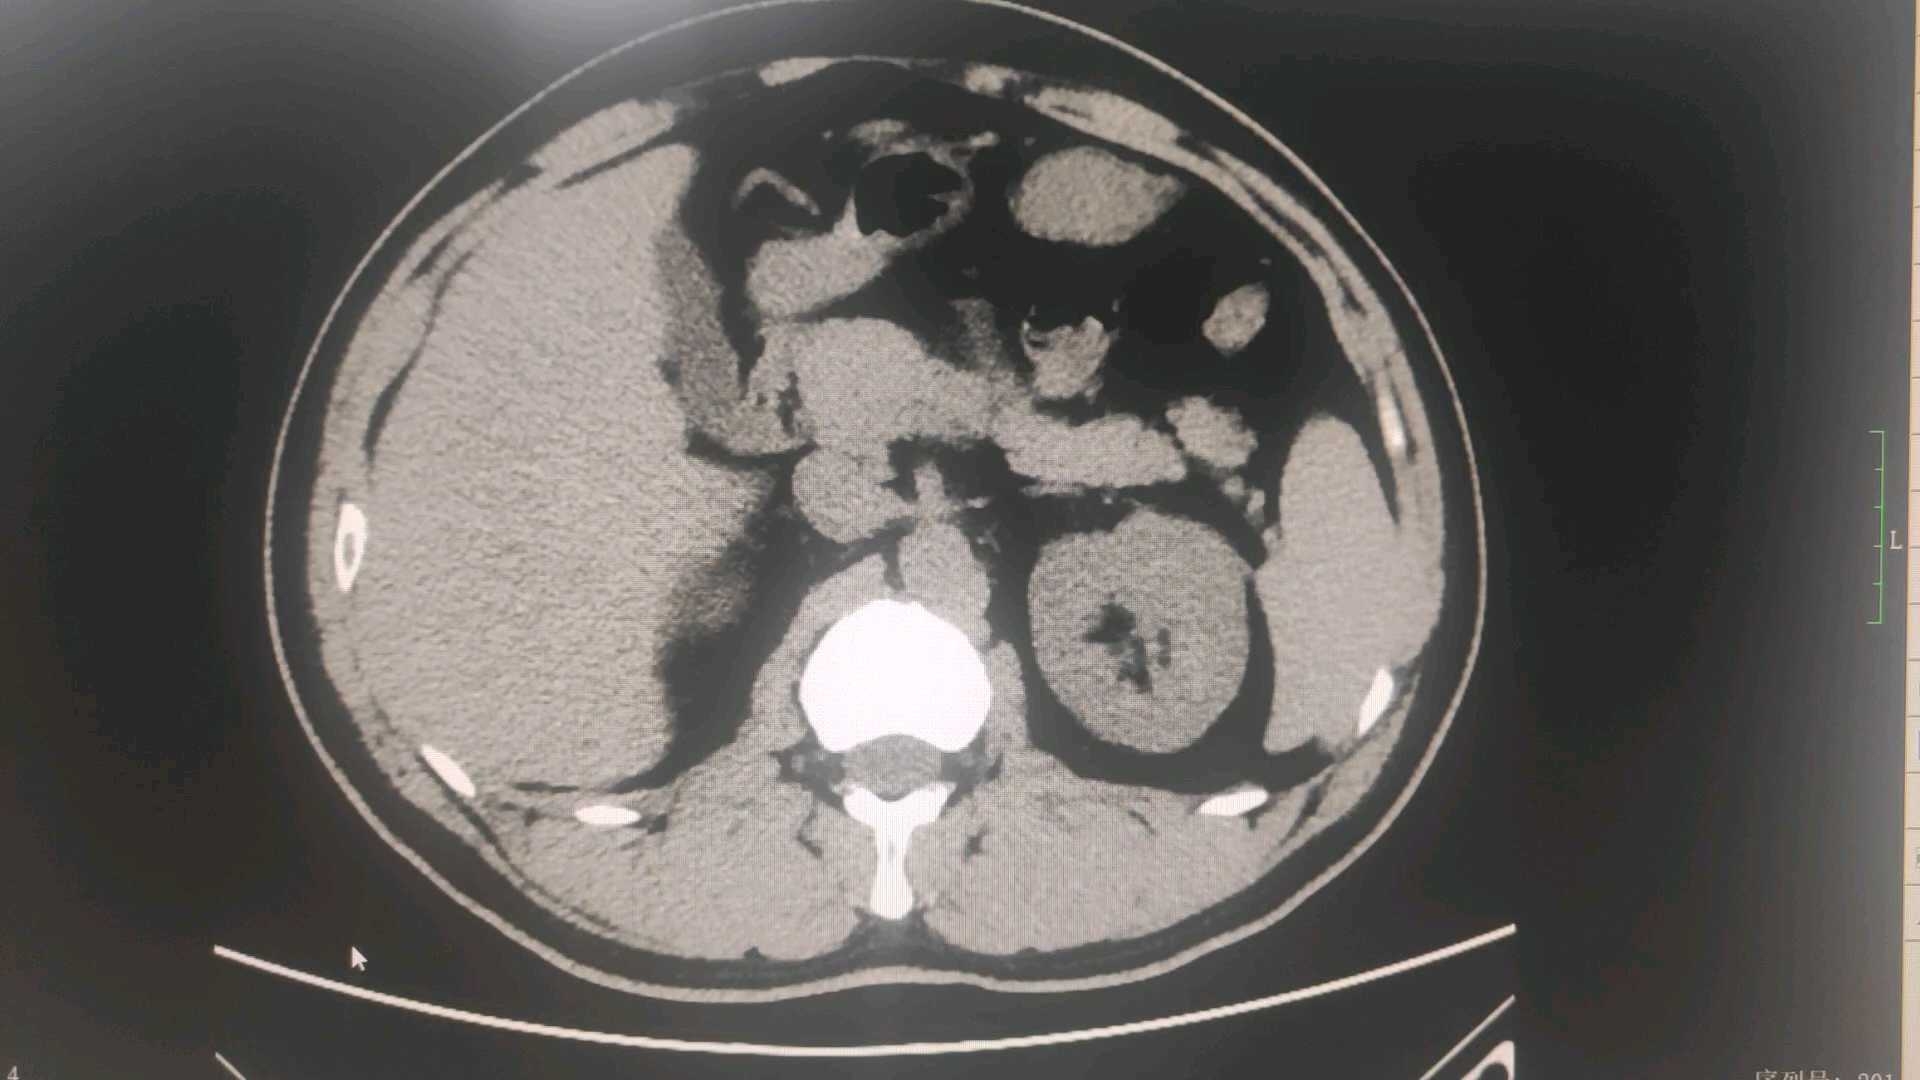

男性,37岁,因“右下腹闷痛2天”于2025-10-25入院,右下腹压痛,反跳痛明显